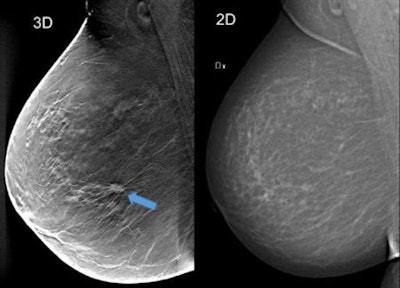

DBT vs. mammography

DBT is emerging as an improved breast cancer screening method, with previous studies showing increased cancer detection compared with traditional mammography. Two-view DBT combined with synthesized digital mammography, which uses 2D images reconstructed from the DBT image dataset, has shown promising results in prospective trials and overcomes the problem of increased radiation exposure associated with combining DBT and digital mammography.

To further simplify breast cancer screening using DBT, the prospective, population-based Malmö Breast Tomosynthesis Screening Trial (MBTST) investigated single-view DBT (mediolateral oblique [MLO] view) compared with conventional two-view digital mammography.